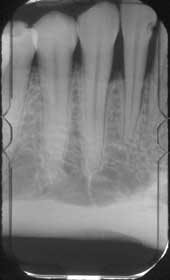

Lower anteriors

The lower anteriors follow the same technique of casting a shadow on the film. The four anteriors should be recorded on one film. Place the short end of the film in the Styrofoam holder. Encourage the patient to relax to enable comfortable placement of the film. Gently bring the film opposite the four anteriors as you have the patient gently bite on the holder. This relaxes the muscles in the floor of the mouth and minimizes the discomfort of the film placement.

The X-ray head should have been set at -15 degrees and moved close to the patient's head. The arch should be parallel to the floor when the patient bites on the holder. Aim the tube so that the beam will pass through the lower four incisors perpendicular to the film and the faces of the teeth. Use of the holder ensures recording of the full view of the incisal and apices of the teeth.

The angulations of the X-ray head given here are averages. You should consult the manual of the equipment manufacturer for more exact angulations recommended for the X-ray being used.

The canine view is also taken at -15 degrees. By now, you have gained experience in efficiently bringing the head of the machine near the patient's head, placing the film so that the canine is in the middle of the film, and aiming the tube so that the beam passes through the middle of the tooth. This completes the periapical full-mouth series.